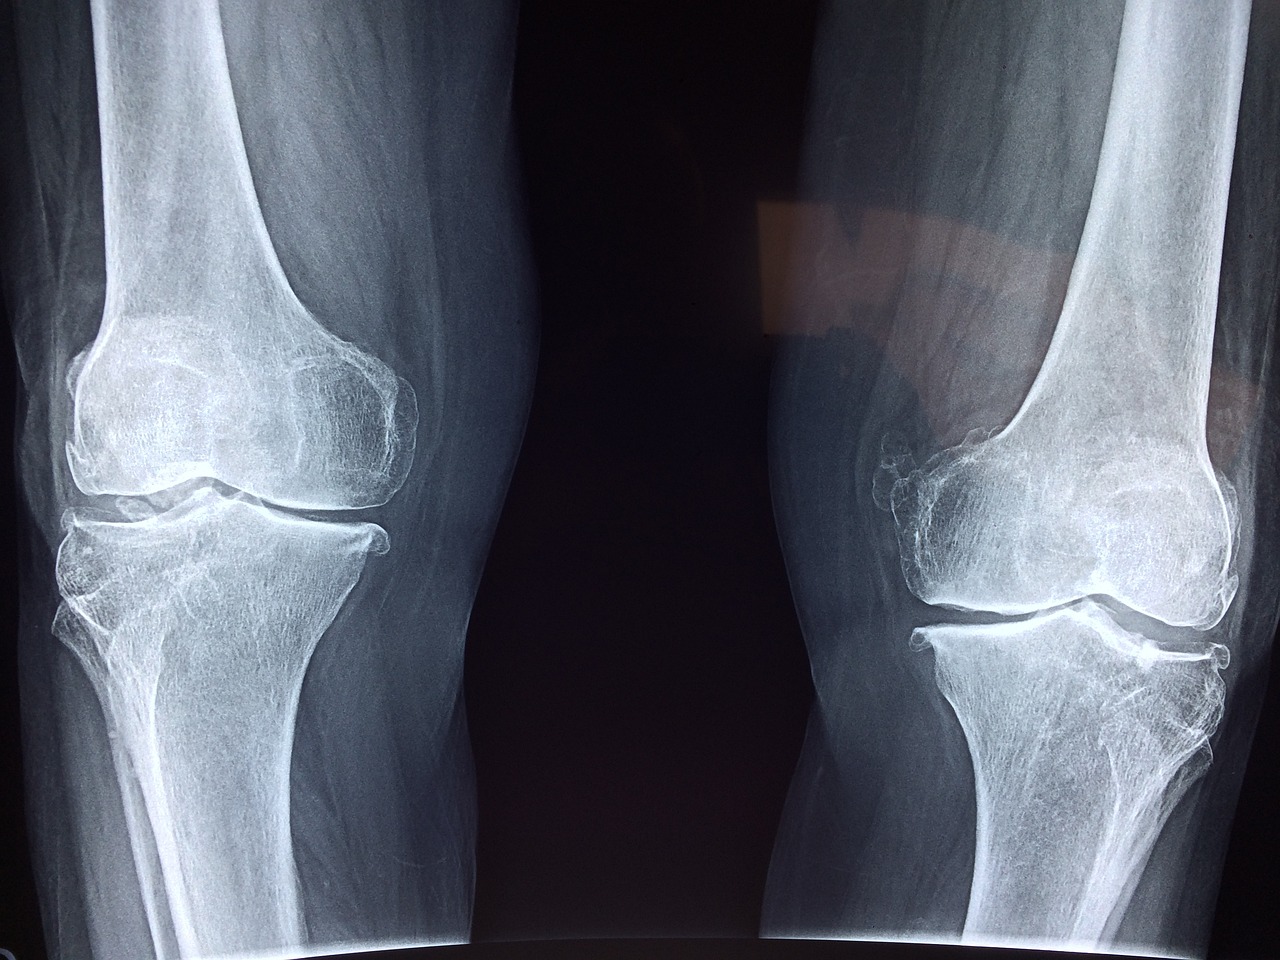

골다공증의 그림자가 다가오기 전에, 뼈 약화의 징후를 알아차리는 법

일상 속에서 문득 느껴지는 작은 통증, 자꾸 부서지는 손톱, 쉽게 쑤시는 무릎...

혹시 우리 몸이 뼈의 이상을 알려주고 있는 건 아닐까요?